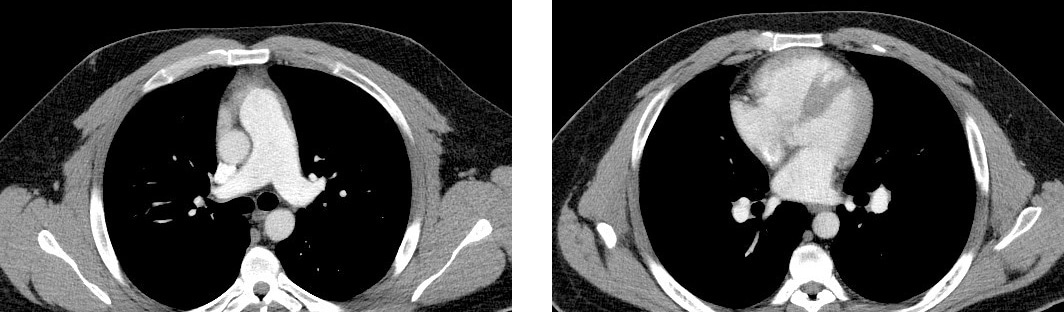

Kate’s CT

Though Kate had had a CT scan, she had never been given a ventilation/perfusion (V/Q) scan to rule out chronic thromboembolic pulmonary hypertension (CTEPH, Group 4).

According to the World Symposium on Pulmonary Hypertension and largely based on findings reported by Tunariu et al (2007), CT pulmonary angiography has a sensitivity of only 51% for CTEPH, compared with the V/Q scan’s sensitivity for CTEPH of 96% to 97%.1 That’s why the V/Q scan is the preferred and recommended screening tool for CTEPH.2

A CT scan may show CTEPH disease, but it may be unremarkable